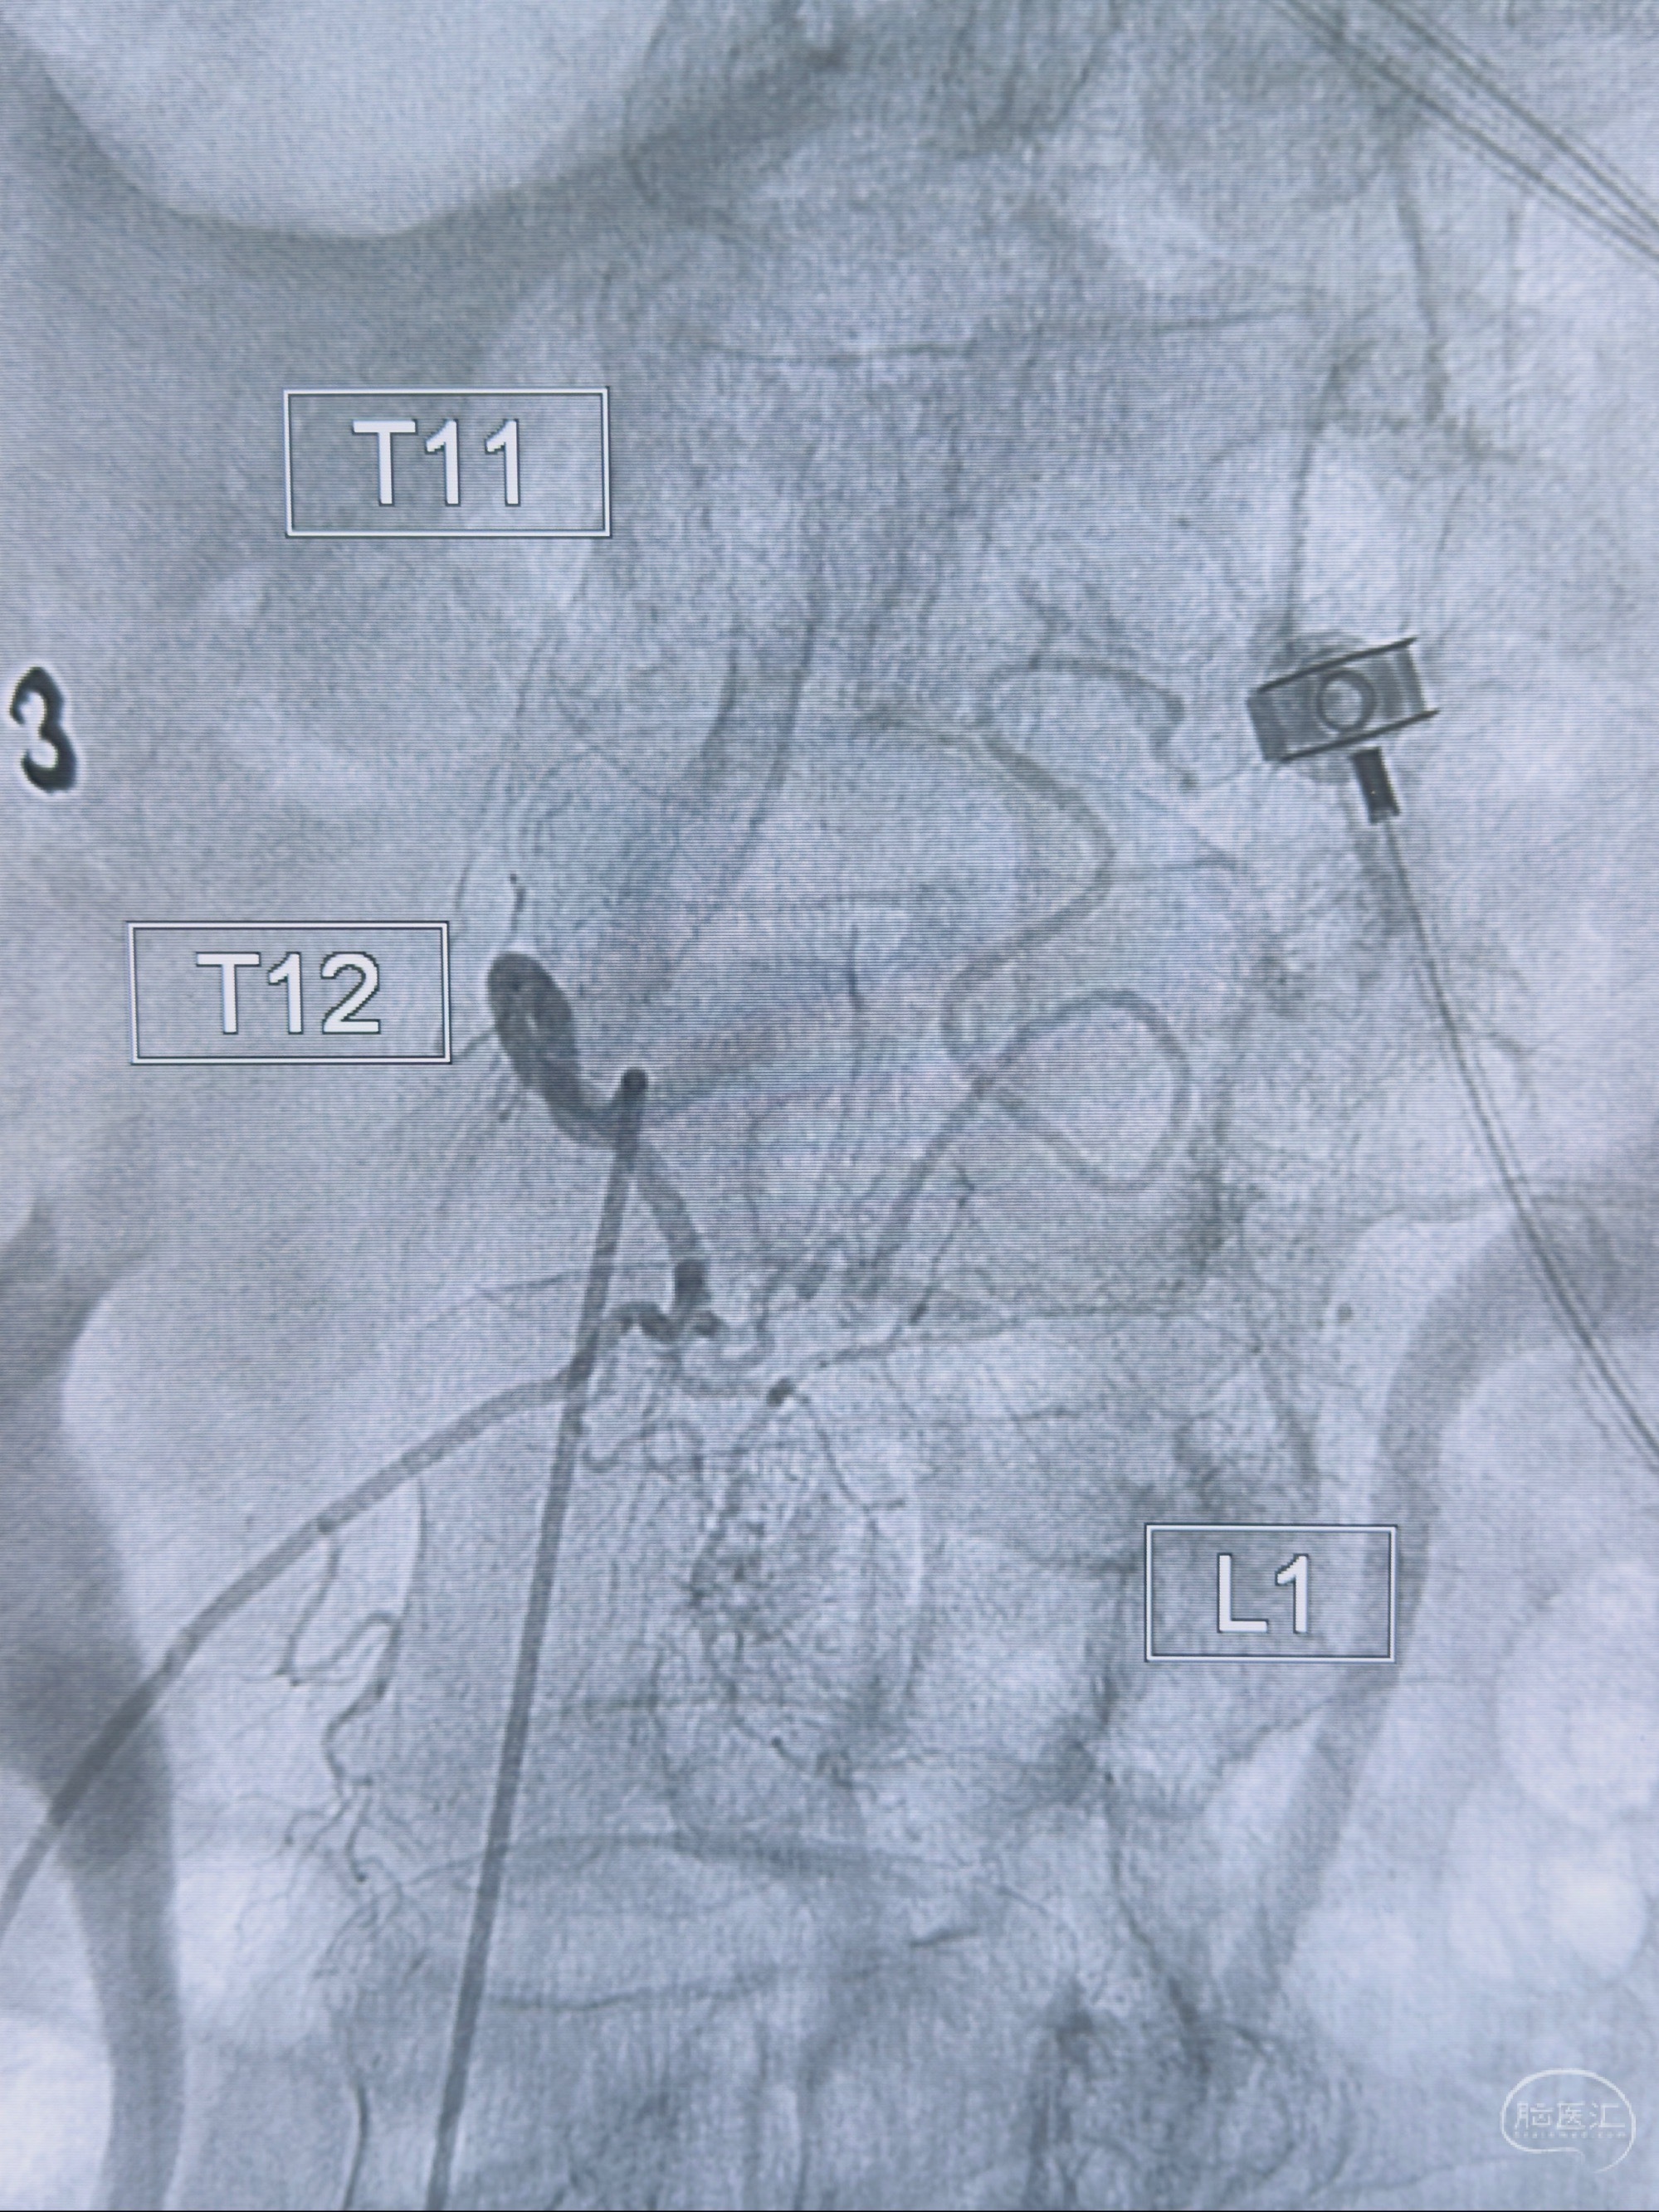

2023-10-13DSA:右侧L1水平硬脊膜动静脉瘘,供血动脉为右侧L1,附近动脉未见明确吻合供血,供血动脉处可见脊髓前动脉发出